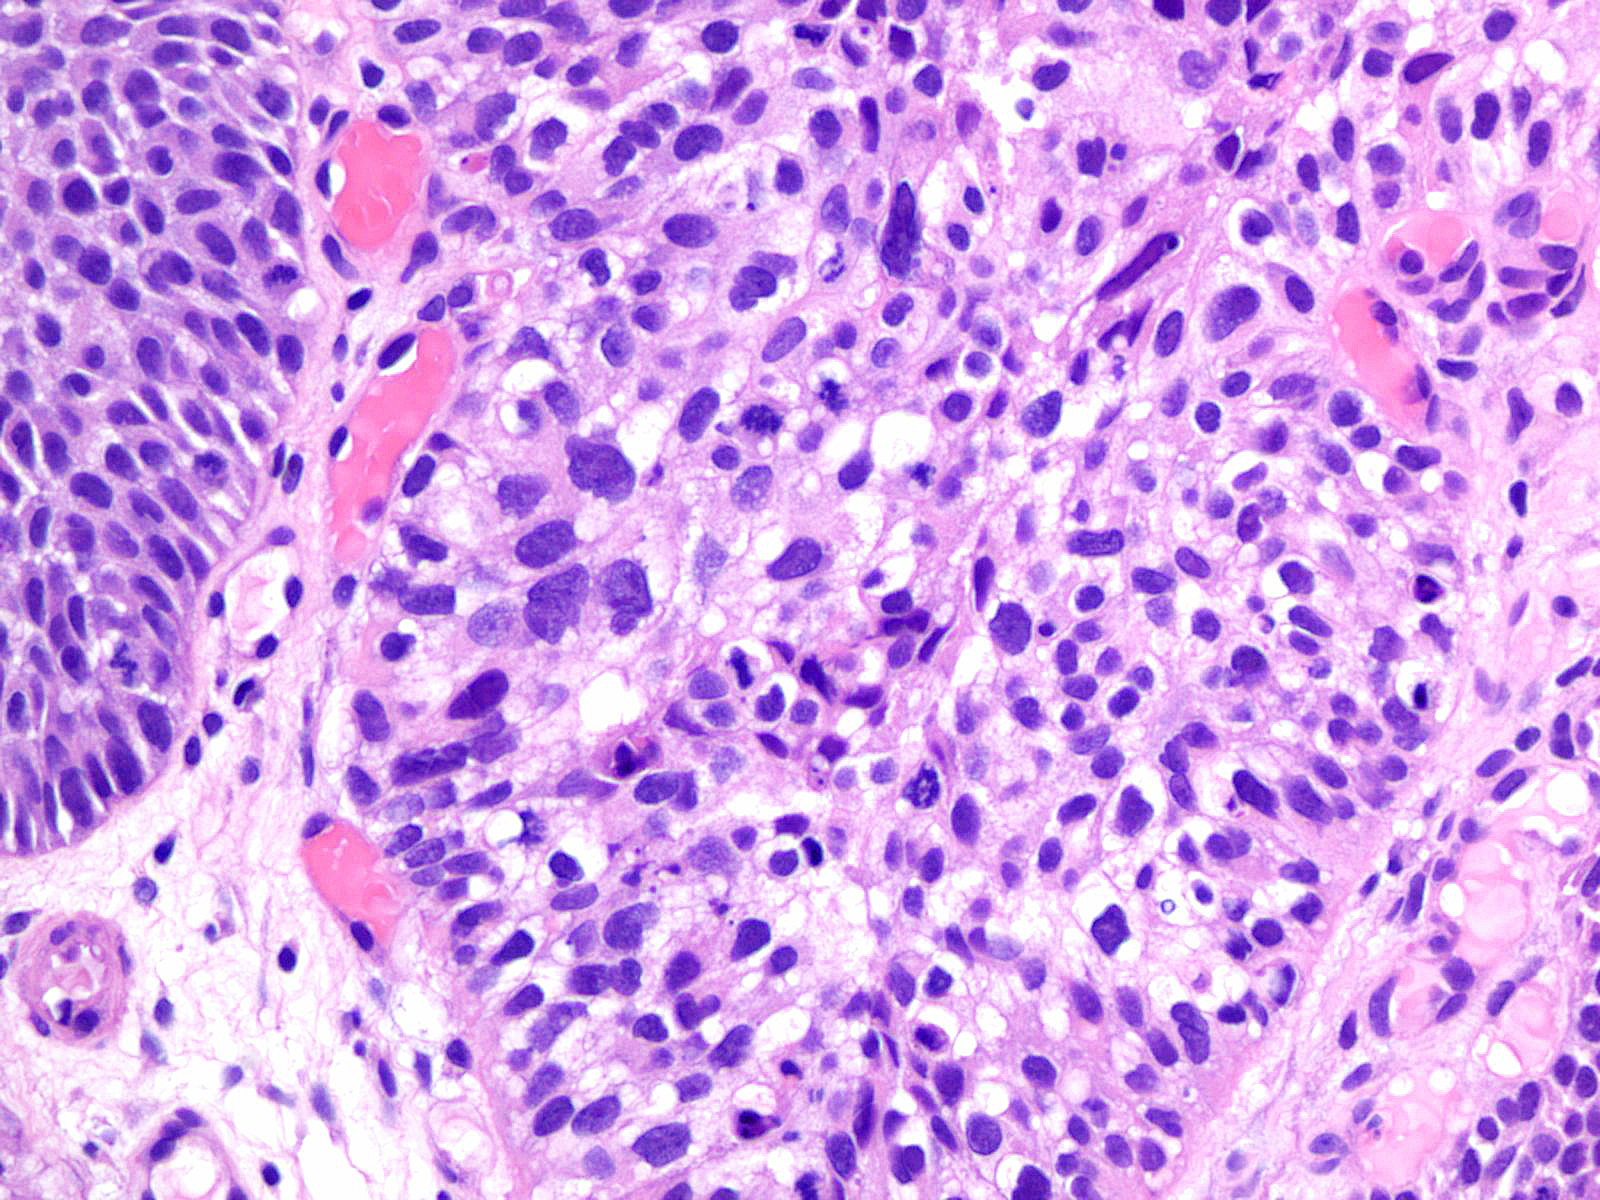

Bladder Papillary Lesions

Case ID: 193